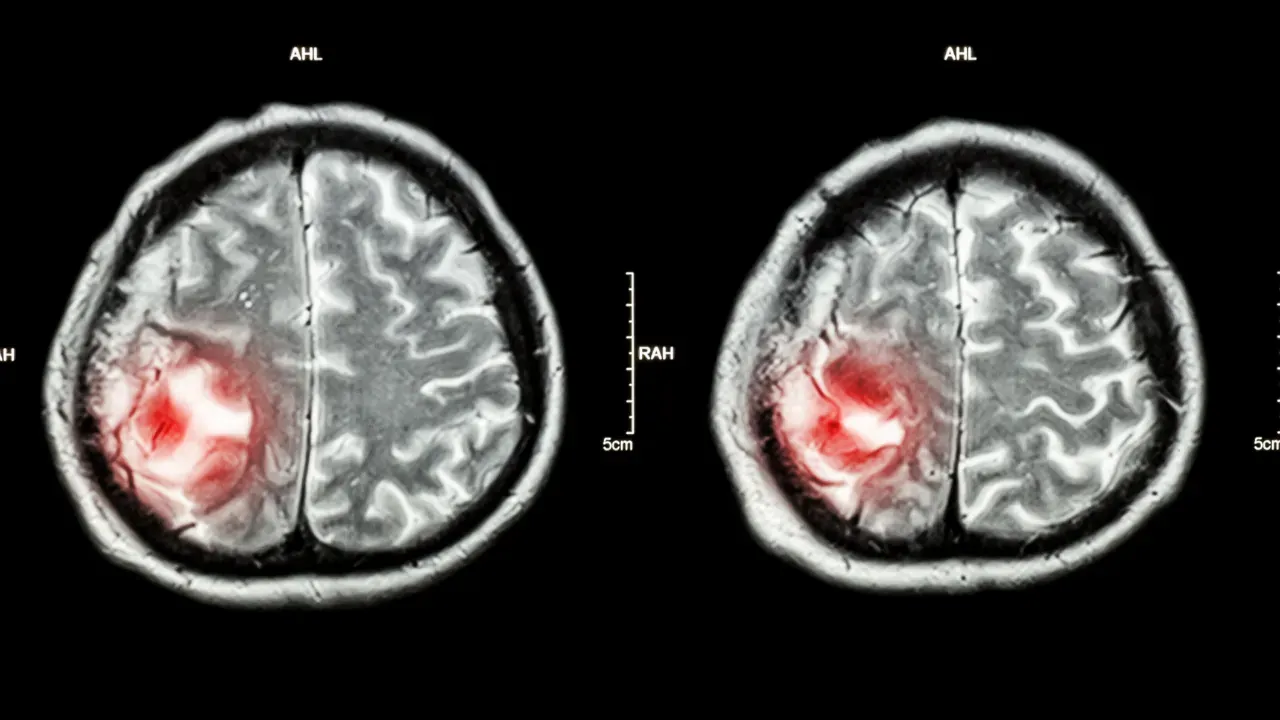

Beyin MR'ında Lezyon Ne Anlama Gelir?

Beyin MR'ında "lezyon" ifadesi, normal beyin dokusundan farklı görünen bir bölgeyi (genellikle T2/FLAIR sekanslarda parlak, hiperintens leke veya odak) tanımlar. Radyologlar bunu şu şekilde yorumlar:

Kitle / nodül → Tümör, kist veya apse şüphesi

Kanama / hemorajik lezyon → İnme veya travma sonrası

MR raporu genellikle "non-spesifik beyaz madde lezyonu", "vasküler kökenli değişiklik" veya "patolojik lezyon" gibi ifadelerle geçer. Kesin anlamı ve tehlike derecesini belirlemek için nörolog veya beyin cerrahı değerlendirir; bazen kontrastlı (ilaçlı) MR, PET-CT veya biyopsi gerekebilir.